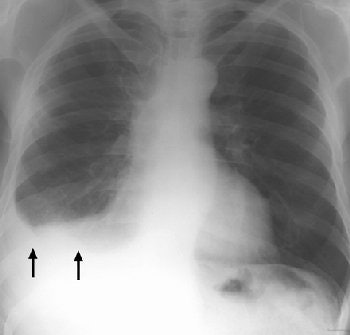

| Posteroanterior radiograph of an asbestos-exposed patient shows a right-sided pleural effusion (arrows). Figure 1, Roach HW, Davies GJ, "Asbestos: When the Dust Settles -- An Imaging Review of Asbestos-related Disease" (RadioGraphics 2002; 22: S167-S184). |

What does an x-ray reveal to a B reader looking at an asbestos-related case? The features of asbestosis on a chest radiograph include "ground-glass opacification, small nodular opacities, and 'shaggy' cardiac silhouette, and ill-defined diaphragmatic contours," wrote Roach's group in RadioGraphics (October 2002, Vol. 22: special issue, pp. S167-S184).

In terms of pleural plaques, the classic distribution on x-ray is seen on the posterolateral chest wall between the seventh and tenth ribs, the lateral chest wall between the sixth and ninth ribs, and the dome of the diaphragm, Roach stated. Pleural plaques are the most common manifestation of asbestos exposure.

In cases of malignant mesothelioma, the chest x-ray generally reveals an effusion, pleural thickening, and a contracted hemithorax.